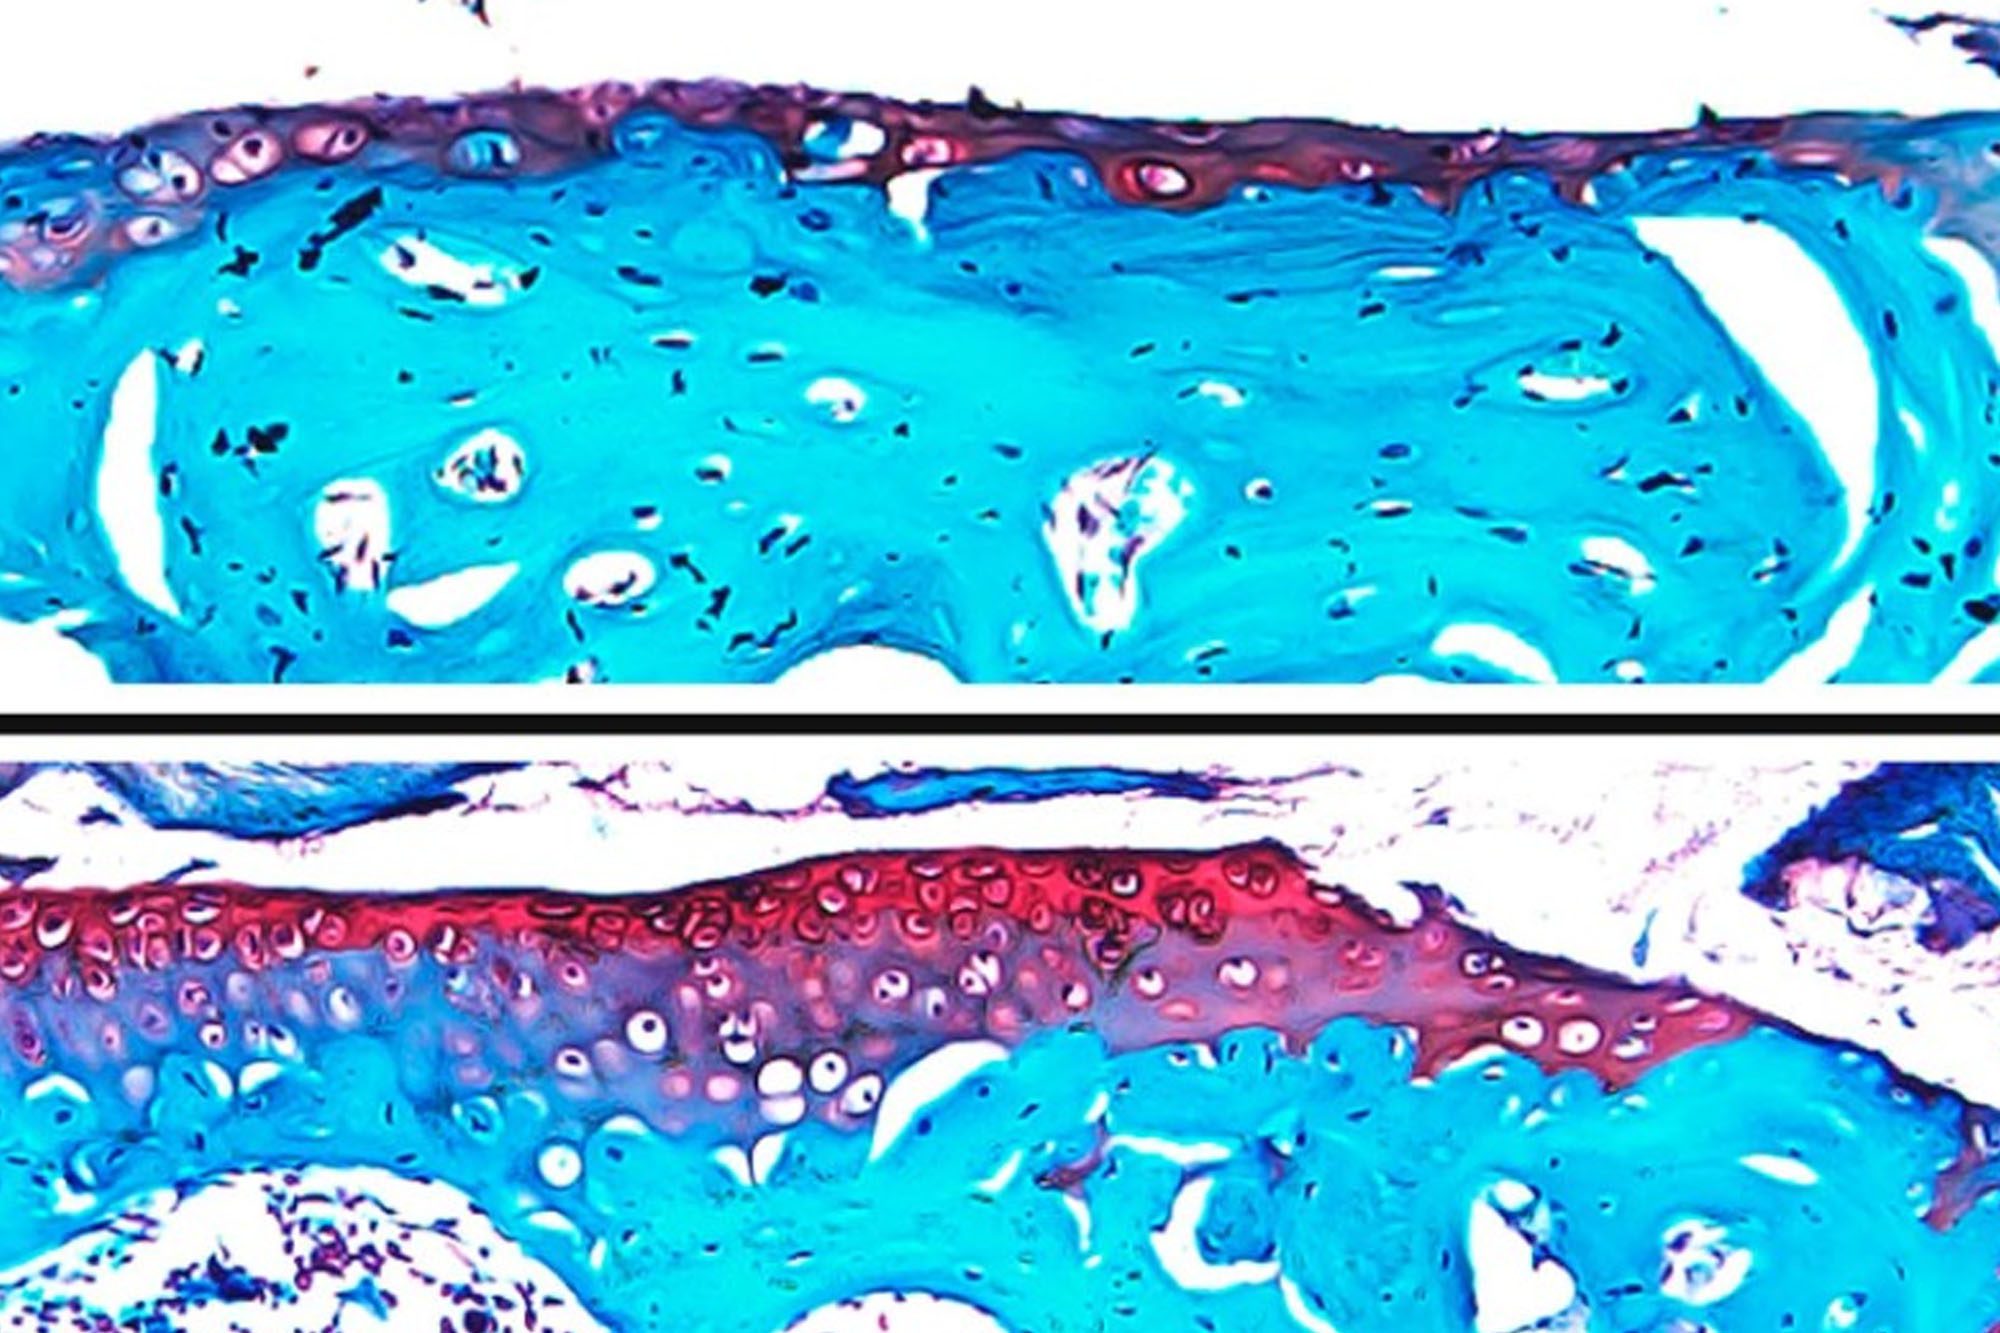

Lewis Lab investigates intriguing role of osteocytes in bone health

A special type of cell, called an osteocyte, may hold the key to some of the mysteries of osteoporosis. A research group led by Karl Lewis, assistant professor of biomedical engineering, is studying osteocytes in unique new ways.